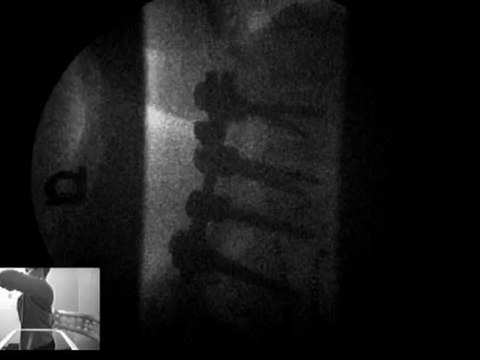

Herniated disc? Pinched Nerves? Low Back Pain? <br /><br />Get out of pain naturally! Call 360-798-4175 for an appointment today. Fast relief from back pain, headaches, and neck pain! Our office, DMX of Vancouver, concentrates on low back pain using the DRX 9000. We use cutting edge diagnostic and treatment machines to get you better

Cutting My Low Back Open for Surgery